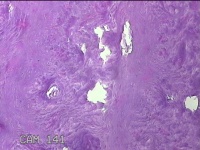

左腕掌侧结节

性别

男

年龄

57岁

临床诊断

皮下结节

一般病史

近3个月来,发现左腕掌侧一结节,无明显疼痛及不适。

标本名称

大体所见

灰白暗红色皮肤样结节1.5x0.8x0.3cm一个,表面糜烂,切面灰白暗红色,质软。

图1